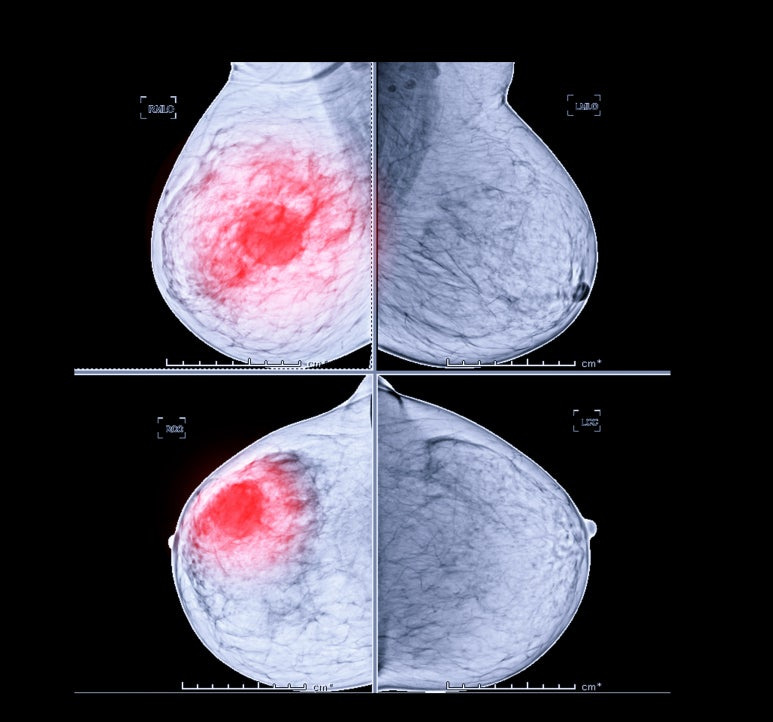

유방암은 유방 조직 내의 세포가 비정상적으로 증식해 종양을 형성하는 질환이에요. 대부분 유관(젖샘관)이나 소엽에서 발생하며 암세포가 주변 조직이나 다른 장기로 전이될 수 있어 조기 진단과 치료가 무엇보다 중요합니다.